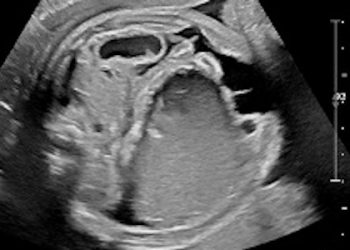

How To Do Agosto 2021: Cesarean Scar Pregnancy

Cari soci, questo mese un nuovo video "How to do", sulla diagnosi ecografica di gravidanza su cicatrice di pregresso taglio...